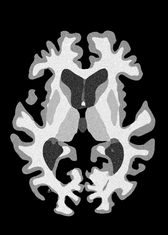

4.2 Registration to a 100 micron ex-vivo brain MRI volume

To showcase the efficacy of our method on real large scale images, we register a 250 in-vivo MRI image (Lüsebrink et al., 2017) to a 100 ex-vivo FLASH human brain volume (Edlow et al., 2019). This represents an inverse problem with more than 11.2B optimizable parameters (compared to 20M for clinical datasets), or 44.8GB of GPU memory. The entire problem does not fit on most GPUs, necessitating distributed multimodal registration. We optimize a composite transform - affine followed by a diffeomorphic mapping; details can be found in Section E.1. Multimodal deformable registration took 58 seconds on 8 NVIDIA A6000 GPUs, which is unprecedented at this resolution. Fig. 6 shows qualitative results, highlighting the ability to register highly detailed structures such as cerebellar white matter; these structures are not visible at macroscopic scales. The resultant advantages of performing registration at this scale can allow researchers to characterize the neuroanatomy at microscopic resolutions and allow morphometric analysis of cortical layers and subcortical nuclei among other structures.